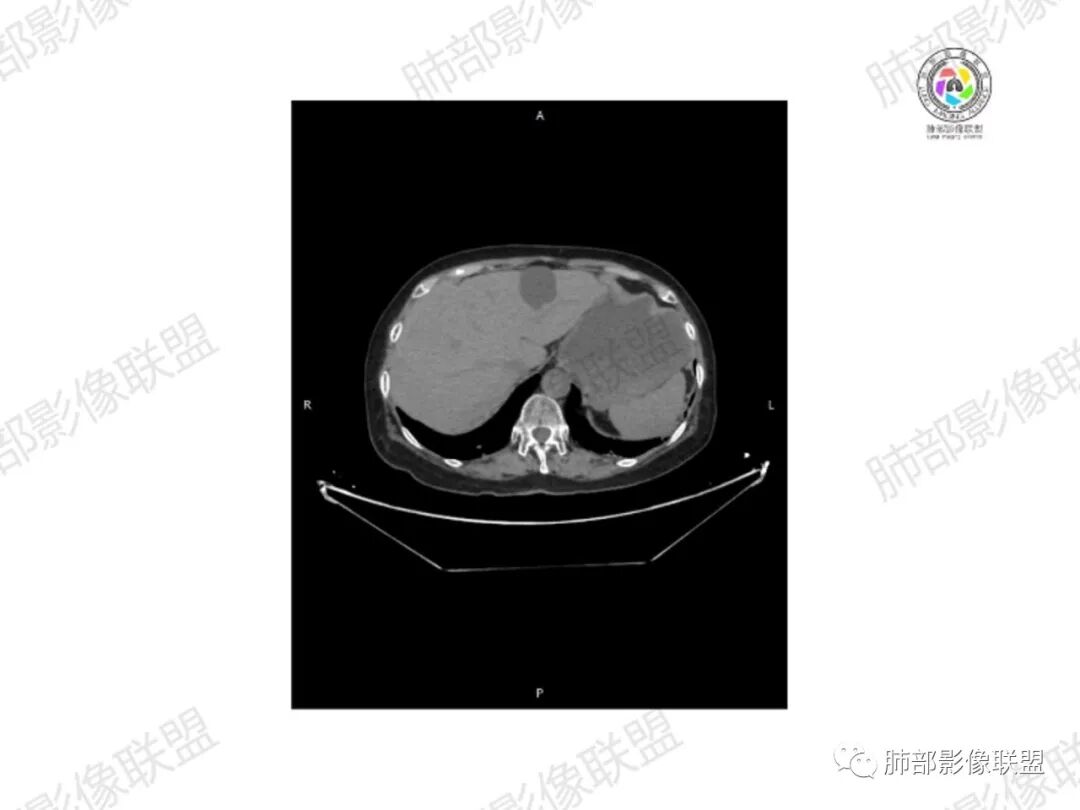

2.右髂骨轻度变形伴广泛骨质吸收破坏,边界不清且突破骨皮质。近中线区以溶骨性破坏为主,髂骨翼一侧则成骨性改变明显,骨表面见垂直骨针或花边样高密度瘤骨。

3.患骨多处皮质断裂,符合病理性骨折。注意折端可能会形成骨痂,但本例无论是形态还是部位都不符合骨痂。

4.患骨两旁(即盆骨内外)见边界不清的较大范围软组织快影,其间偶见骨化影。

5.双肺多发类圆形结节影,边界清楚,随机分布,其间多见钙化密度影。

1.边界不清的骨质吸收破坏,溶骨明显,骨皮质突破,软组织肿块,种种迹象表明其恶性无疑!

2.但注意这是有“成骨”的恶性骨肿瘤!我们知道老年患者的骨原发性恶性肿瘤“成骨”非常少见。少数转移瘤可为成骨型或混合型,女性患者如乳腺癌骨转移等。在男性,最典型的成骨转移是前列腺癌。

本例右侧髂骨具有较为典型的“骨肉瘤”影像学特征,有边界不清的吸收破坏、有新生骨、形成软组织肿块等等。